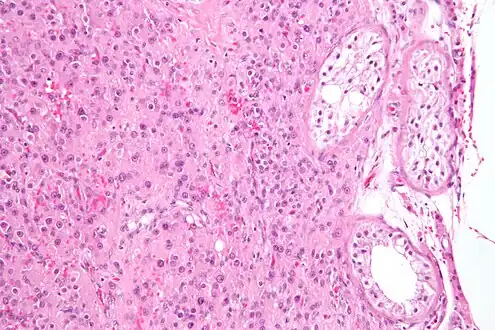

Micrograph showing a cluster of Leydig cells (center of image). H&E stain.

Leydig cells, also known as interstitial cells of the testes and interstitial cells of Leydig, are found adjacent to the seminiferous tubules in the testicle and produce testosterone in the presence of luteinizing hormone (LH).[1][2] They are polyhedral in shape and have a large, prominent nucleus, an eosinophilic cytoplasm, and numerous lipid-filled vesicles.[3]

The mammalian Leydig cell is a polyhedral epithelioid cell with a single eccentrically located ovoid nucleus. The nucleus contains one to three prominent nucleoli and large amounts of dark-staining peripheral heterochromatin. The acidophilic cytoplasm usually contains numerous membrane-bound lipid droplets and large amounts of smooth endoplasmic reticulum (SER).[4] Besides the abundance of SER with scattered patches of rough endoplasmic reticulum, several mitochondria are also prominent within the cytoplasm. Reinke crystals have lipofuscin pigment and rod-shaped crystal-like structures 3 to 20 micrometres in diameter.[5]